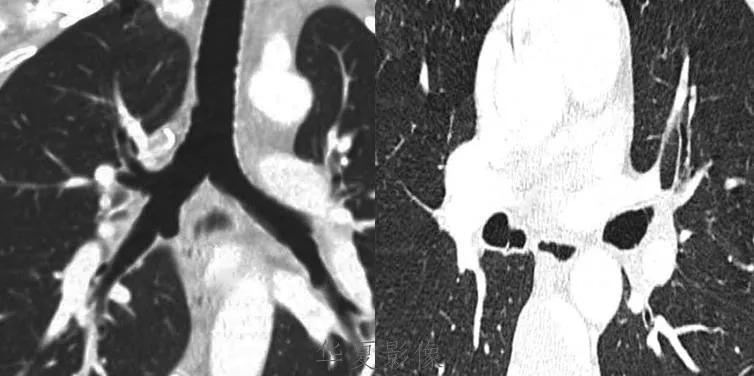

侵袭性胸腺瘤CT图像

a. CT平扫示肺动脉与胸骨间肿块,密度尚均匀,形态不规则b. CT增强示肿块不均匀强化,见低密度囊变区域,肿块与肺动脉之间脂肪间隙消失,肺动脉壁模糊。